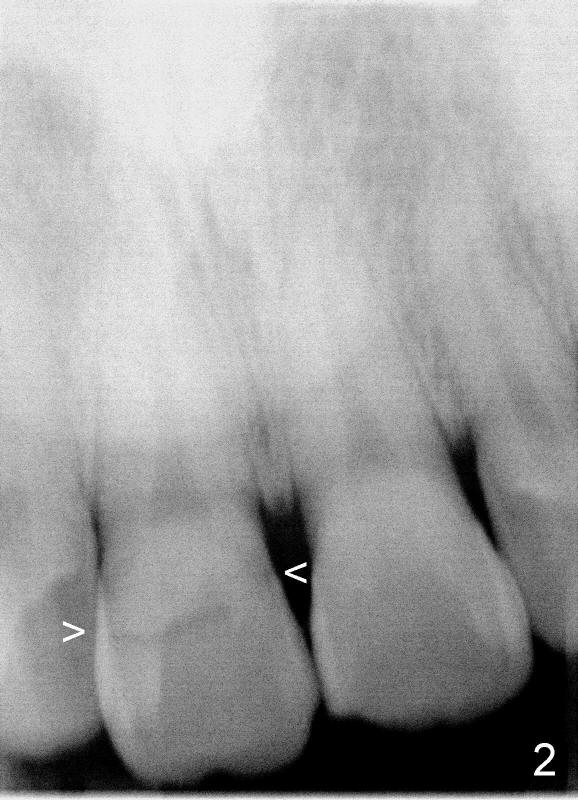

A 55-year-old man has severe pain on the upper right central incisor (Fig.1 *) after biting on a piece of bone. PA confirms crown fracture (Fig.2 <), extending subgingivally (Fig.3 >>). Osteotomy forms using a 2 mm pilot drill and 2.5-3.5 mm reamers (Fig.4). A 5x17 mm Tatum tapered implant is placed, autogenous bone placed in the buccal gap, sutures placed for wound approximation and 3.5 mm 20º angled abutment installed (Fig.5). An immediate provsional is fabricated (Fig.6), cemented and splinted (Fig.7).,